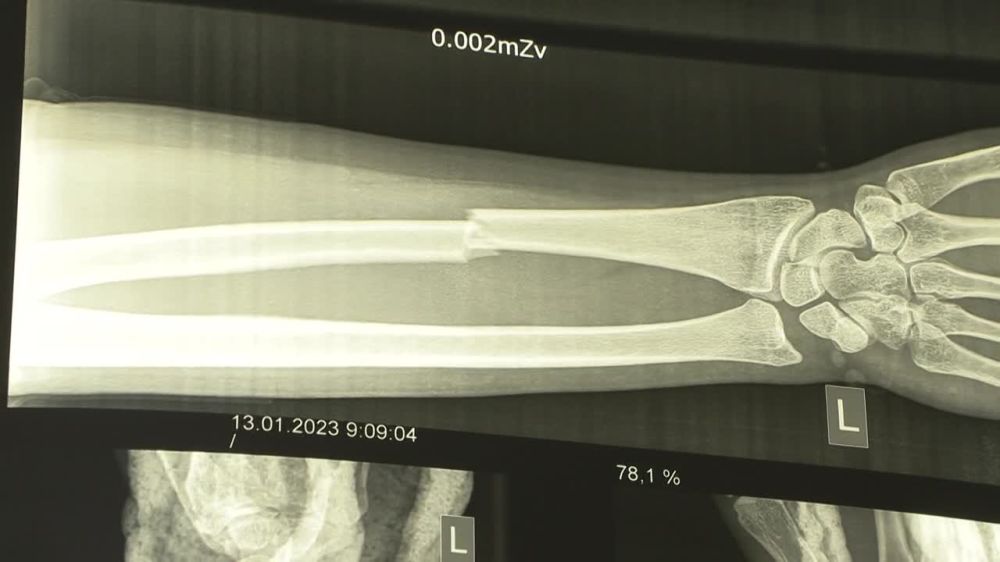

В Тирасполе девушка утром вышла за продуктами, поскользнулась и получила закрытый перелом лучевой кости со смещением. На следующей неделе её будут оперировать. Дальше – гипс и реабилитация. Вернуться к привычной жизни она сможет только через...